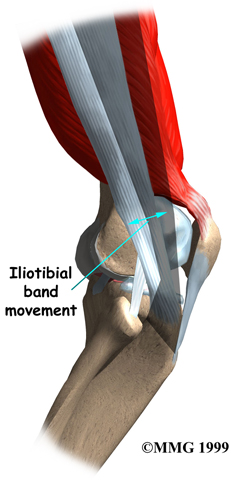

The lower end of the ITB passes over the outer edge of the , the area where the lower part of the femur (thighbone) bulges out above the knee joint. When the knee is bent and straightened, the tendon glides across the edge of the femoral condyle.

Normally, this bursa lets the tendon glide smoothly back and forth over the edge of the femoral condyle as the knee bends and straightens.

The ITB glides back and forth over the lateral femoral condyle as the knee bends and straightens. Normally, this isn't a problem. But the bursa between the lateral femoral condyle and the ITB can become if the ITB starts to snap over the condyle with repeated knee motions such as those from walking, running, or biking.